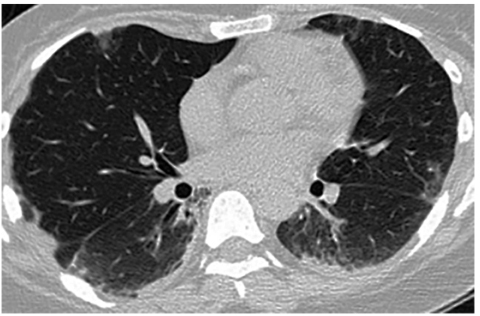

3.1周后复查肺CT(2018-04-08):气胸基本吸收,双下肺实变影及斑片影明显吸收,双肺胸膜下可见磨玻璃影和间质性改变,胸膜局限性增厚(图2)。肺部病灶较前明显改善,提示治疗有效。

图2伏立康唑治疗1周后复查胸部CT:右侧气胸基本吸收,双下肺实变影及斑片影明显吸收,双肺胸膜下可见磨玻璃影和间质性改变,局限性胸膜增厚